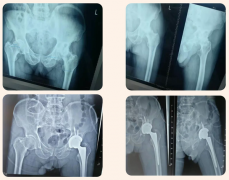

臨滄市中醫醫院骨科成功開展全髖關節置換術。...